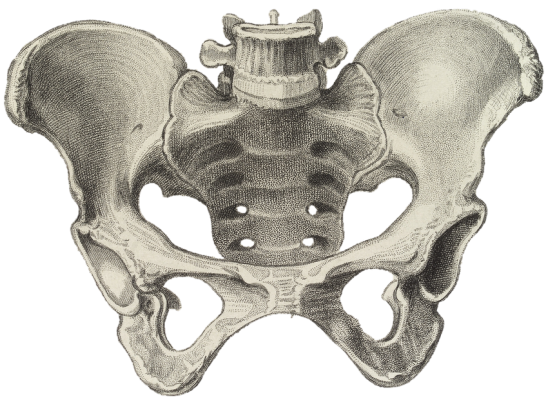

Pochopenie príčin bolesti kostrče

Coccydynia, bežne nazývaná bolesť kostrče, sa vzťahuje na pretrvávajúcu bolesť na samom spodku chrbtice. Táto bolesť sa môže vyvinúť po priamej traume alebo spontánne bez špecifického vyvolávajúceho… Viac

Pochopenie sakroiliitídy: Je to typ artritídy?

Sakroilitída aj artritída končia príponou „itída“, čo znamená zápal. Sakroilitída postihuje sakroiliakálny (SI) kĺb, a hoci nejde o typ artritídy, je spojená so zápalovou artritídou chrbtice. Aký je… Viac